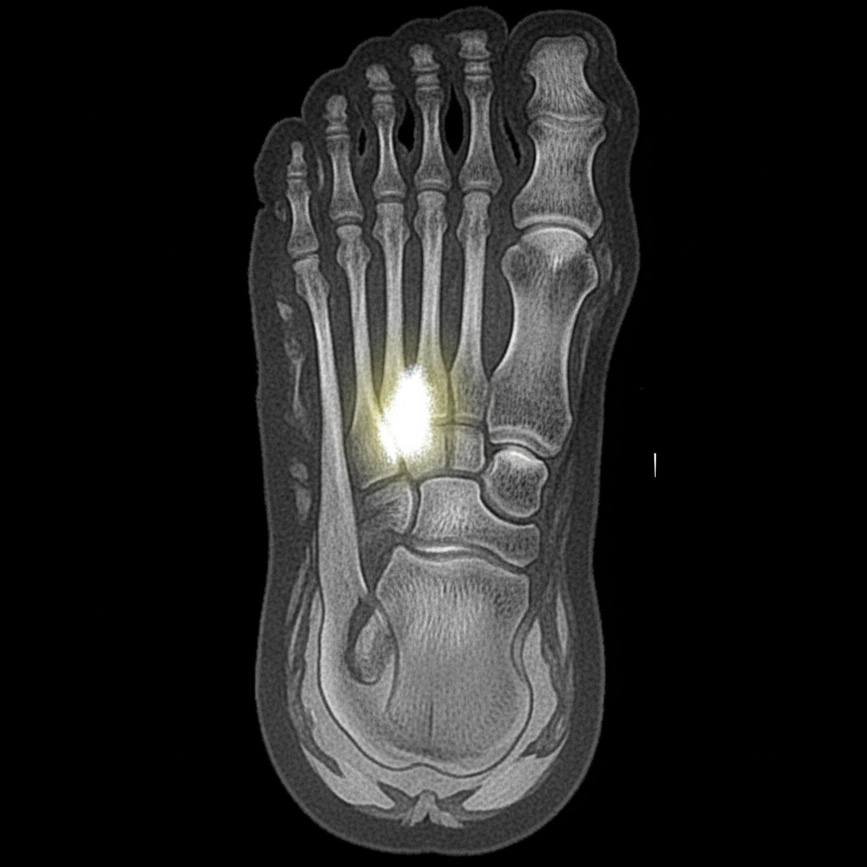

Le pied représente la localisation la plus fréquente. Cette fatigue osseuse survient lorsque le processus de réparation naturel ne compense plus les micro-dommages. Les zones vulnérables incluent le métatarse du pied, le tibia, le péroné et parfois le genou. Découvrez notre contenu traitant de la prise en charge de kinésithérapie du genou.

Le diagnostic d’une fracture de fatigue exige une approche rigoureuse. L’examen clinique révèle une sensibilité localisée précise. La radiographie représente l’examen de première intention, mais présente une limite : les petites fissures restent invisibles pendant les premières semaines.

L’IRM constitue l’examen de référence pour confirmer le diagnostic rapidement. Elle détecte les modifications osseuses précoces, l’œdème médullaire et les fissures invisibles à la radiographie. Ce diagnostic précoce permet d’initier le traitement adapté.

La guérison d’une fracture de fatigue nécessite entre six et douze semaines en moyenne. Cette durée varie selon la localisation : une fracture de fatigue métatarsienne du pied consolide en six à huit semaines, tandis qu’une fracture du tibia requiert huit à douze semaines.